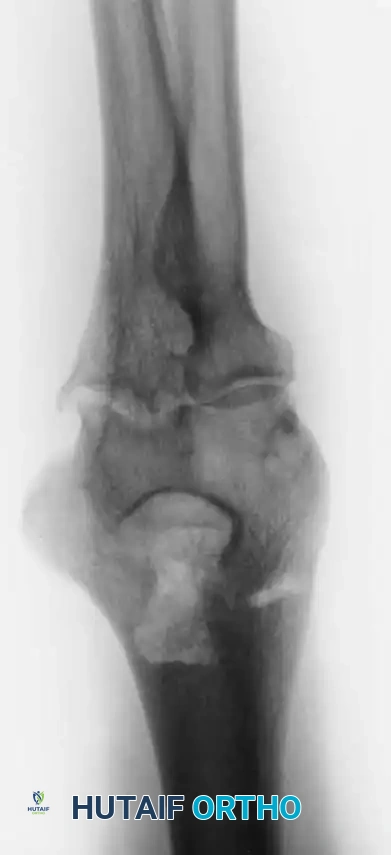

Associated Surgical & Radiographic Imaging